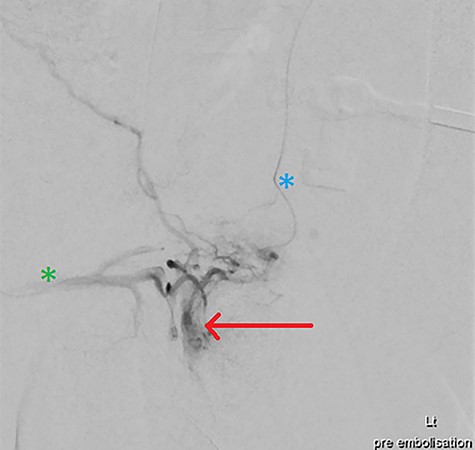

Under general anaesthetic, US-guided puncture of the left common femoral artery (CFA) was performed, with placement of a long 45cm 5-French Flexor-Sheath (COOK Medical). A 0.035 Glidewire (Terumo) and Rim catheter (Merit Medical) was used to go up and over the aortic bifurcation and to cannulate the right internal iliac artery. The Rim catheter was exchanged for a Van Schie 2 catheter (COOK Medical), with contrast angiography performed from the origin of the right internal pudendal artery (IPA). A pseudoaneurysm was confirmed, arising from the distal branched vessels of the right IPA, notably with contralateral IPA communication. Using a 0.014 wire and a 150 cm Excelsior SL-10 2.4-French microcatheter (Stryker), the pseudoaneurysm was cannulated, with superselective contrast angiography confirming position (Fig. 3).

DSA via superselective cannulation of the left (blue asterix) and right (green asterix) distal branches of bilateral internal pudendal arteries; note the arterial pseudoaneurysm (red arrow) pre-embolization.